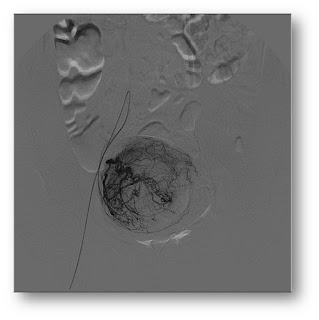

Como é feita e embolização dos miomas uterinos?

A embolização é um procedimento minimamente invasivo que consiste em uma

punção na região da virilha seguido de inserção de um fino catéter que vai até

a região dos miomas. Através deste catéter são injetadas partículas que são

pequenas bolinhas que ocluem a irrigação de sangue para os miomas. Assim os

miomas regridem e deixam de causar sintomas.